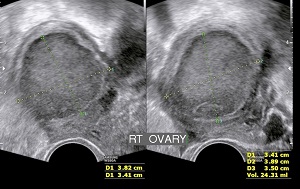

• Sonography: Sonography can confirm the disease, its extent & severity. In uterus , changes may be localized or diffuse.Its presence in ovaries lead to chocolate cyst formation. Endometriotic nodules in pouch of douglas or along walls of uterus with free fluid is a sign of advanced disease.